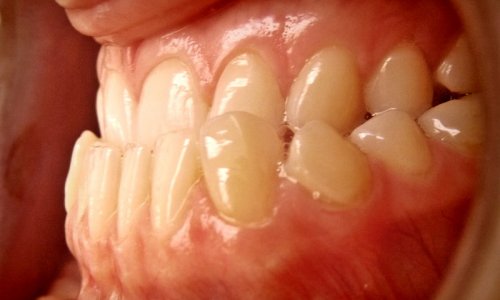

Zgryz Przed

Zgryz

Stan wyjściowy: Widoczna dysproporcja szczęk (progenia) wpływająca negatywnie na profil tkanek miękkich oraz funkcję żucia.